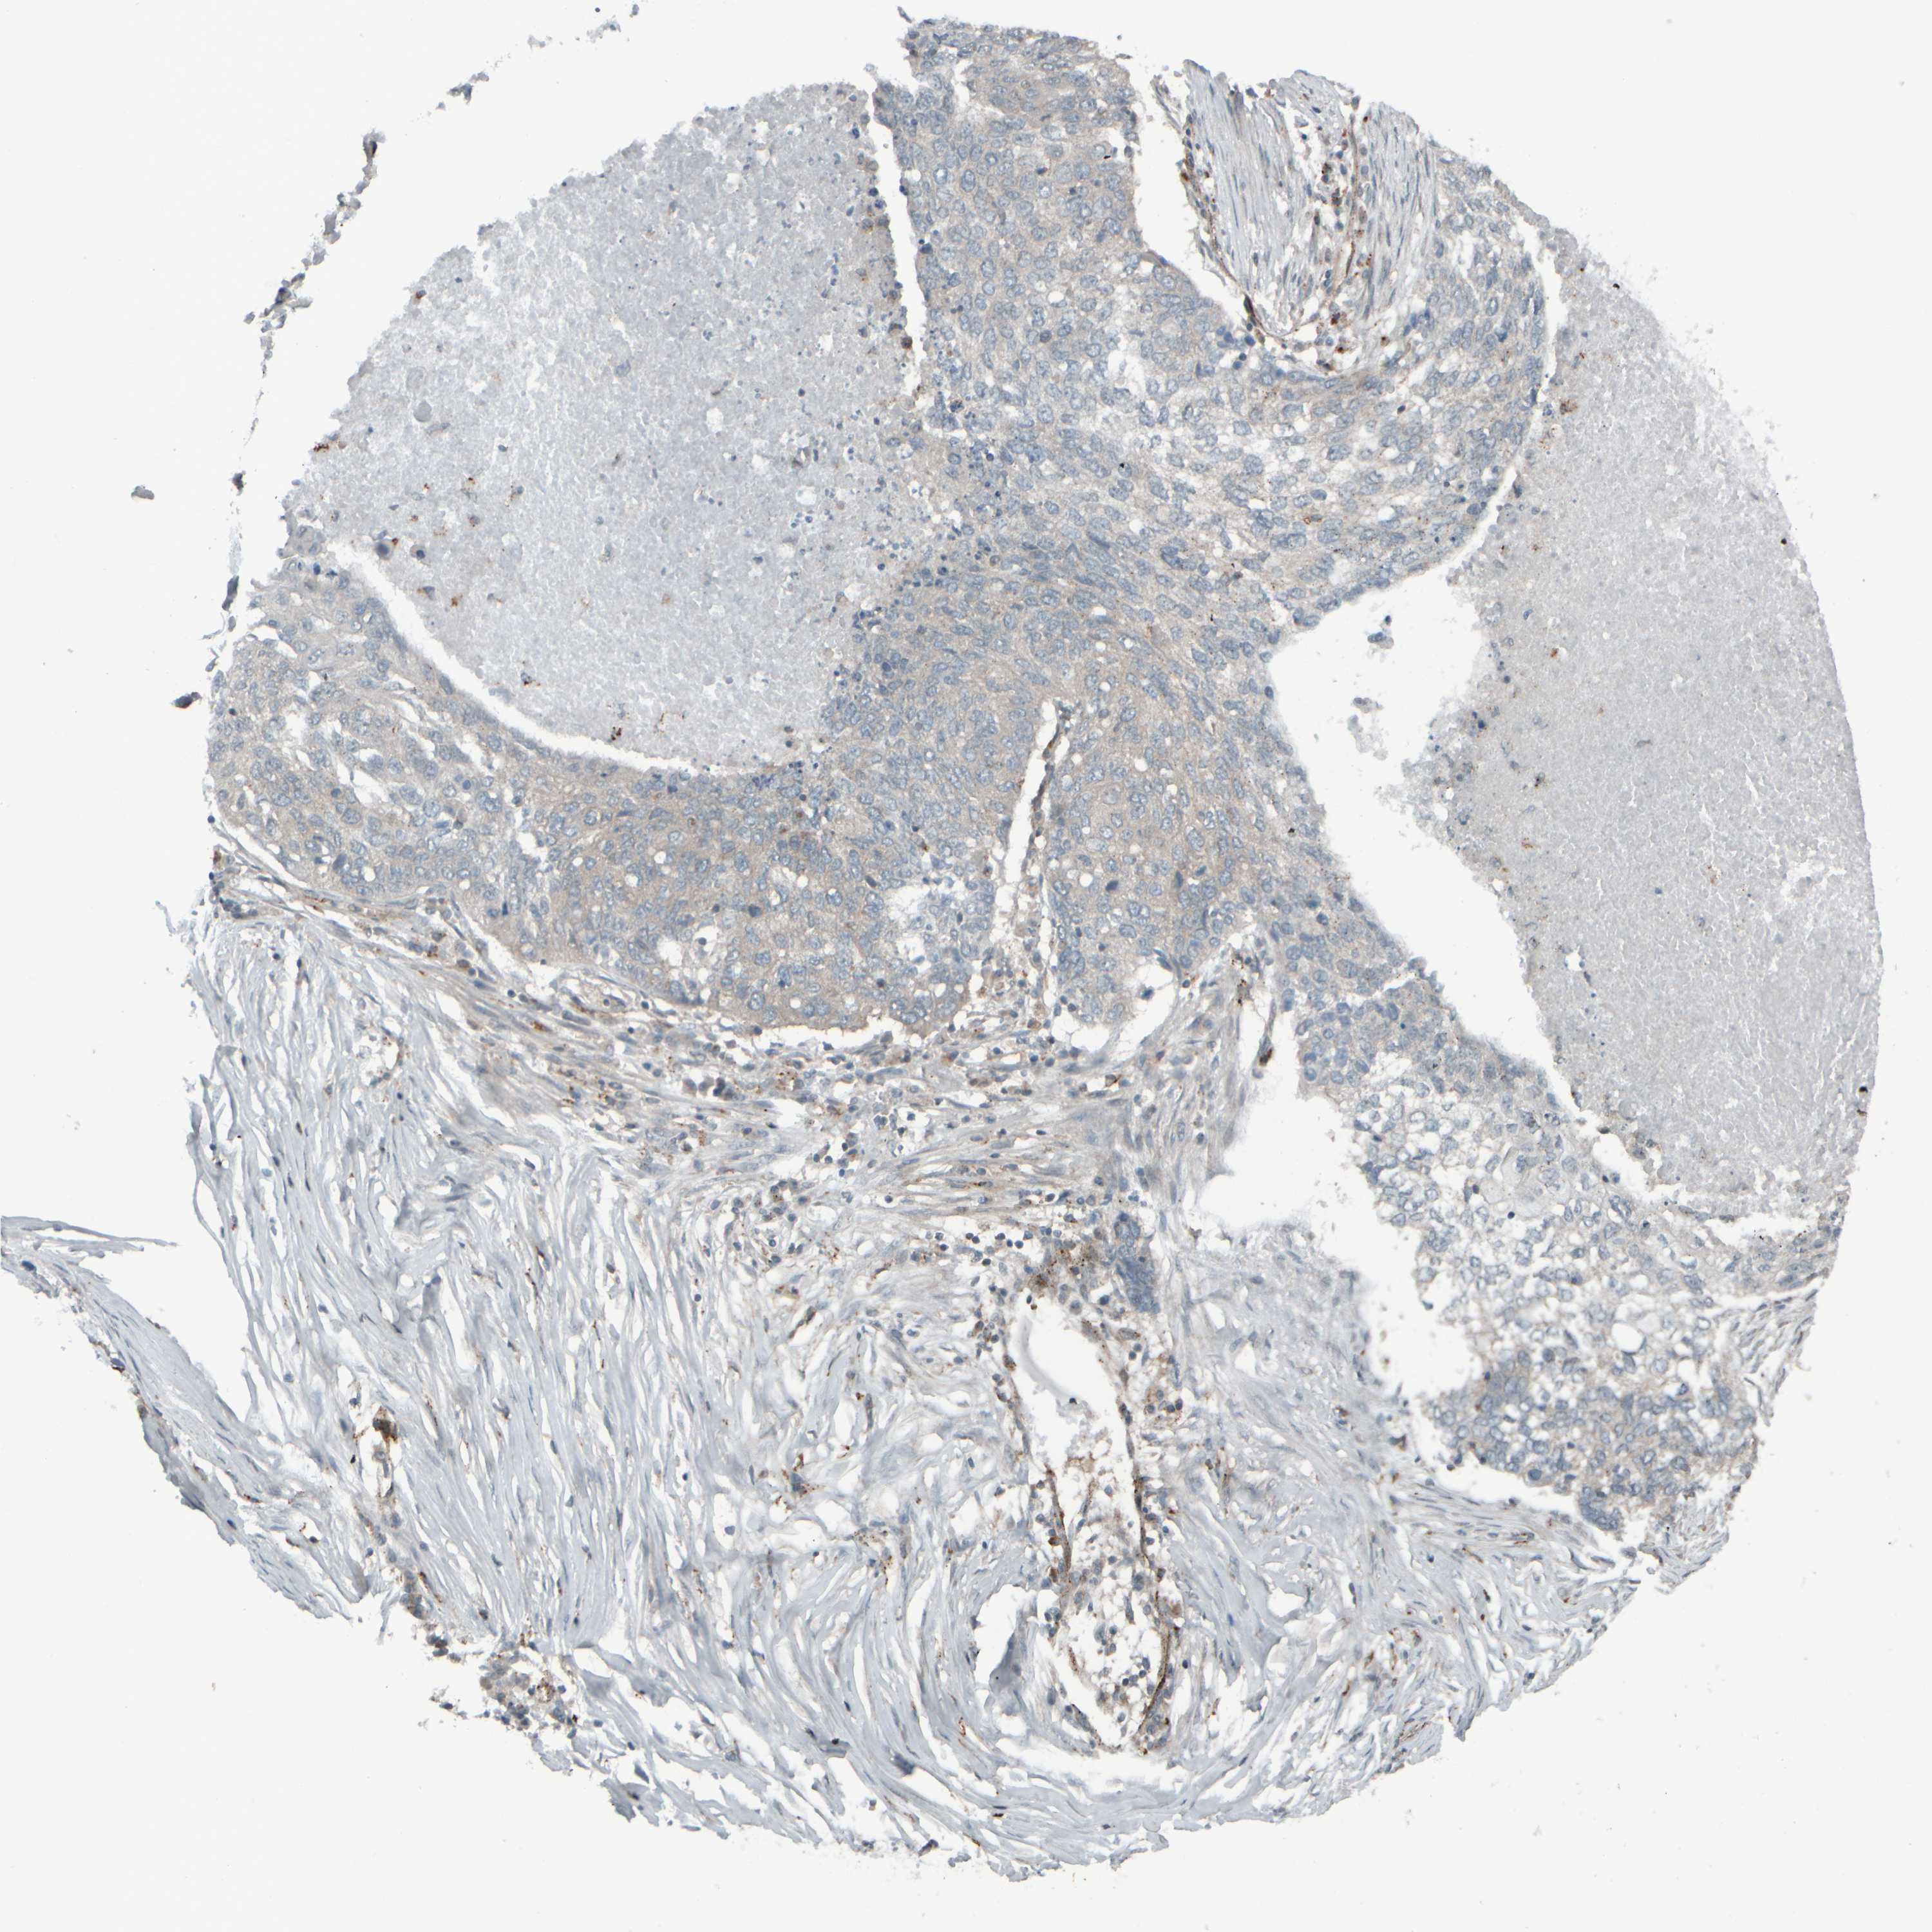

CANCER LUNG CANCER Show tissue menu

LUNG ADENOCARCINOMA (TCGA) - Interactive survival scatter ploti

The Survival Scatter plot shows the clinical status (i.e. dead or alive) for all individuals in the patient cohort, based on the same data that underlies the corresponding Kaplan-Meier plots. Patients that are alive at last time for follow-up are shown in blue and patients who have died during the study are shown in red.

The x-axis shows the expression levels (FPKM) of the investigated gene in the tumor tissue at the time of diagnosis. The y-axis shows the follow-up time after diagnosis (years). Both axes are complimented with kernel density curves demonstrating the data density over the axes. The top density plot shows the expression levels (FPKM) distribution among dead (red) and alive patients (blue). The right density plot shows the data density of the survived years of dead patients with high and low expression levels respectively, stratified using the cutoff indicated by the vertical dashed line through the Survival Scatter plot. This cutoff is automatically defined based on the FPKM cutoff that minimizes the p-score. The cutoff can be changed by dragging the vertical line or by entering a cutoff value in the square labeled "Current cut-off".

Under the Survival Scatter plot the p-score landscape (black curve; left axis) is shown together with dead median separation (red curve; right axis). Dead median separation is the difference in median mRNA expression between patients who have died with high and low expression, respectively. It is calculated as follows: median FPKM expression of dead patients with high expression - median FPKM expression of dead patients with low expression. This is intended to aid the user in visually exploring custom cutoffs and the associated p-scores and dead median separation.

Individual patient data is displayed and can be filtered by clicking on one or more of the category buttons on the top of the page. Categories describing expression level and patient information include: high, low, alive, dead, female, male and tumor stages. The scale of the x-axis can be toggled between linear and log-scale by clicking on the "x log" button. Mouse-over function shows TCGA ID, patient information and mRNA expression (FPKM) for each patient.

& Survival analysisi

Kaplan-Meier plots summarize results from analysis of correlation between mRNA expression level and patient survival. Patients were divided based on level of expression into one of the two groups "low" (under cut off) or "high" (over cut off). X-axis shows time for survival (years) and y-axis shows the probability of survival, where 1.0 corresponds to 100 percent.

GIGYF1 is not prognostic in Lung Adenocarcinoma (TCGA)

: 22.18

Average pTPM 16.9

Number of samples 497